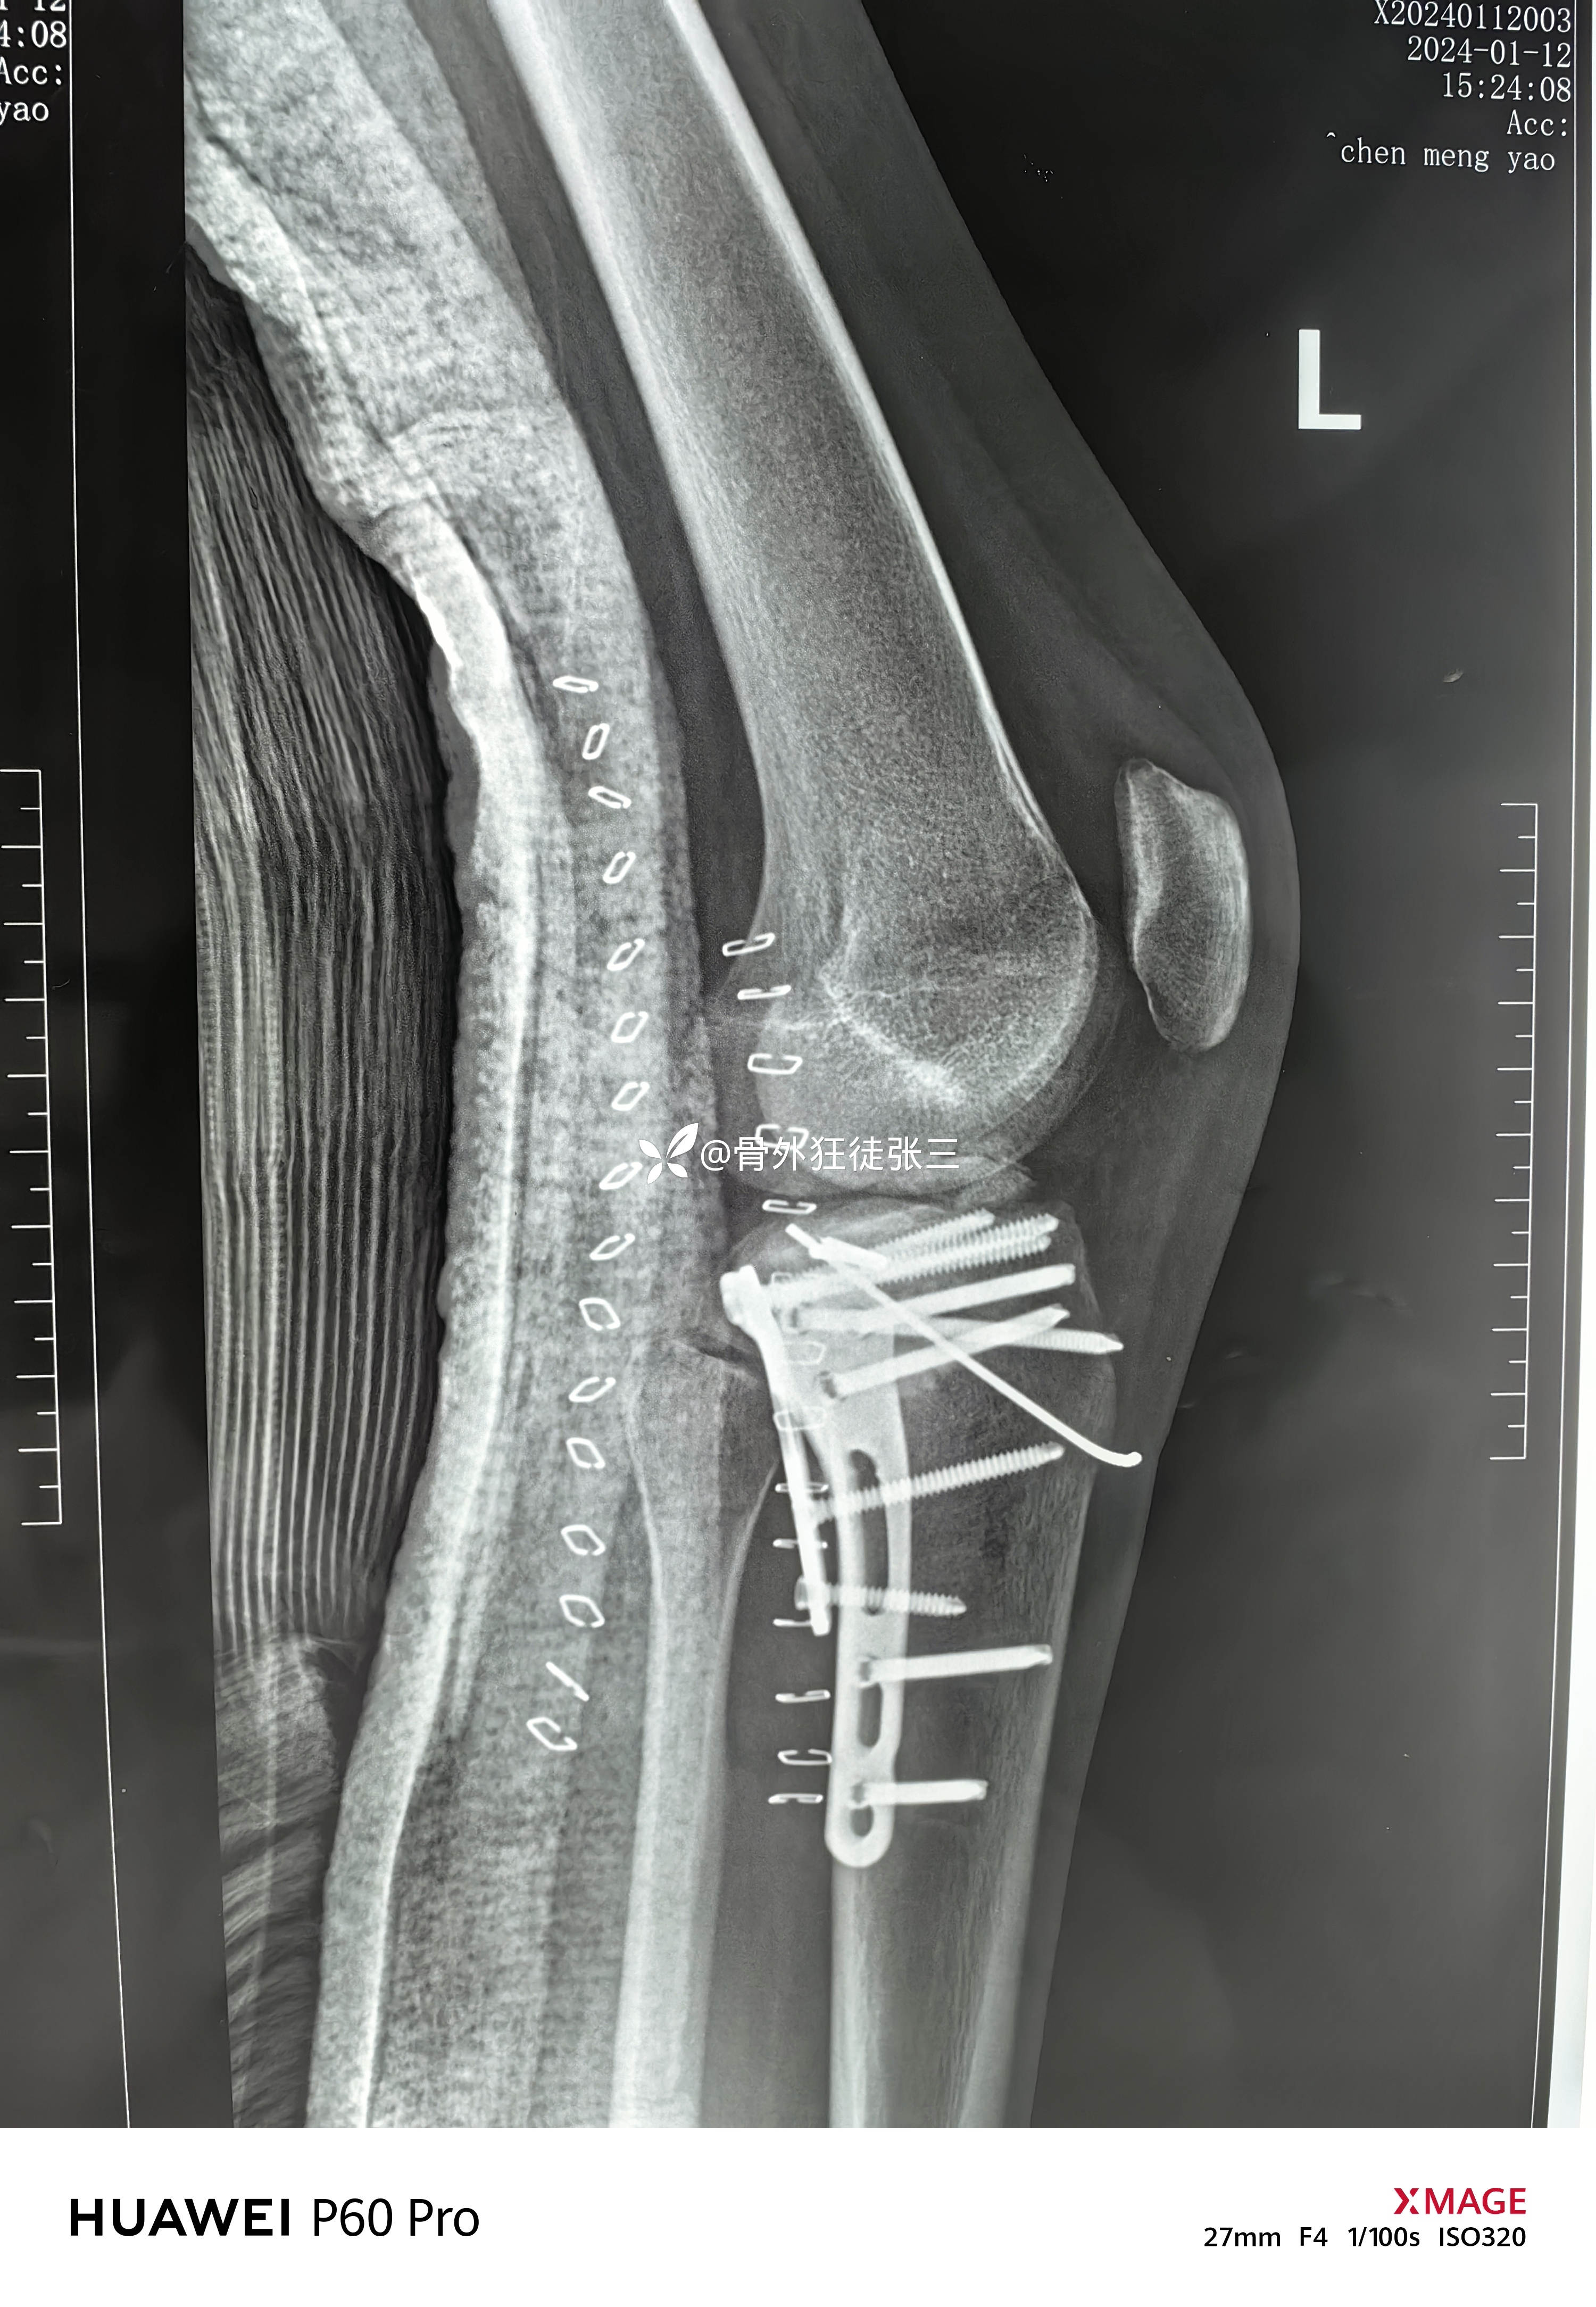

胫骨平台骨折术后,腓总神经损伤,

患者性别:女

患者年龄:19岁

主诉:右胫骨平台骨折术后膝、踝关节活动和感觉障碍3月余。

2023.12.08,在当地医院行胫骨平台骨折手术

2024..01.03,在当地医院行韧带修复术,术后出现感觉和运动障碍

第一次手术后复查

第二次手术后复查